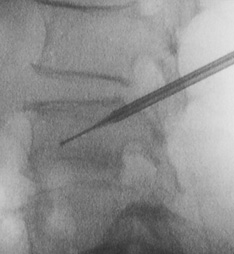

皮下局麻的情况下使用3mm的探针插入压迫的锥体内,再放入骨水泥。30分钟即可完成手术次日便可出院。

术中随时拍下X光照精确确认骨折的部位